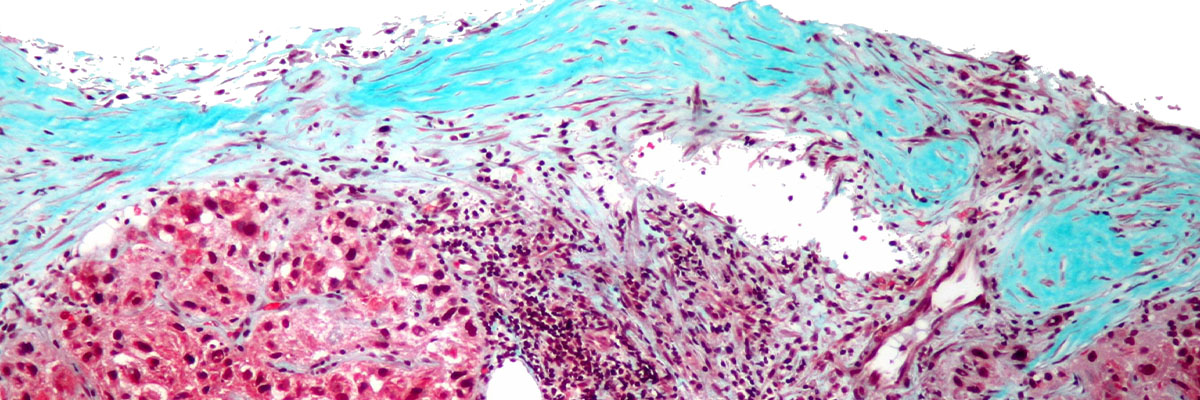

- Hepatocellular carcinoma. Ang kanser na ito ay tinatawag ding hepatoma at kilala rin bilang pinaka-karaniwang uri ng kanser sa atay. Ang kondisyong ito ay namumuo sa mga hepatocyte, o ang pinaka-laganap na uri ng selula sa atay. Ito ay maaaring kumalat mula sa atay papunta sa lapay, bituka, sa tiyan, maging sa ibang pang kalapit na bahagi ng katawan. Ang kanser na ito ay higit na maaaring umapekto sa mga taong may malubhang pinsala sa atay bunga ng pag-abuso sa mga nakalalasing na inumin.

Ang isa sa mga hakbang sa pag-iwas sa kanser sa atay ay ang pag-iwas sa pagkakaroon ng cirrhosis. Ang kondisyong ito ay ang pagkakaroon ng atay ng mga peklat na maaaring humantong sa pagkakaroon ng kanser.